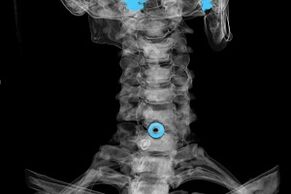

The diagnosis is established based on the characteristic symptoms, in addition to using:

- X-ray. The method is ineffective, especially in the later stages of the development of osteochondrosis.

- MRI (magnetic resonance imaging) of the cervical spine.A method that allows you to see bone structures, intervertebral disc herniations, their size and direction of development.

- Computed tomography.A less effective solution than MRI, since it is difficult to determine the presence and size of hernias.